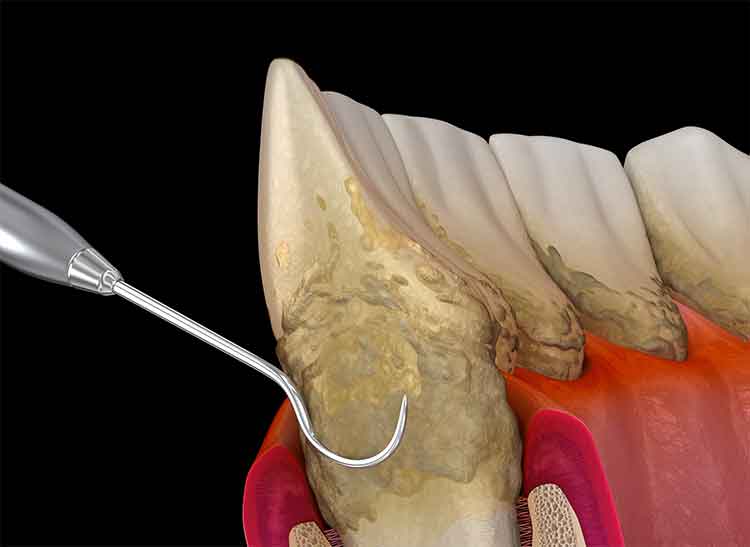

Deep cleaning (scaling and root planing)

A non-surgical procedure that removes plaque and tartar from below the gumline, helping to treat gum disease and promote healing.